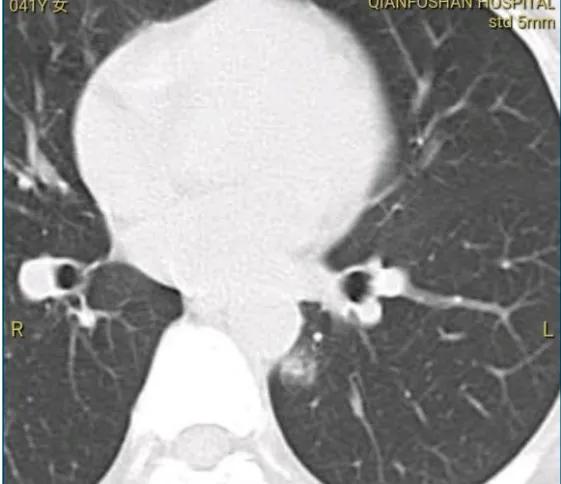

尊敬的戴主任您好,前幾天向您諮詢過。我有0.8cm的純磨玻璃結節,您判斷是微浸潤。我已經做了消融術,您的意見是不長就是安全的,讓我把消融的片子發給您看看,當時還沒做,所以也沒發。現在我做了,麻煩您看一下:

消融灶隨訪吧,沒有長大,暫時可以不手術。若心理壓力大就楔形切除小手術切掉。